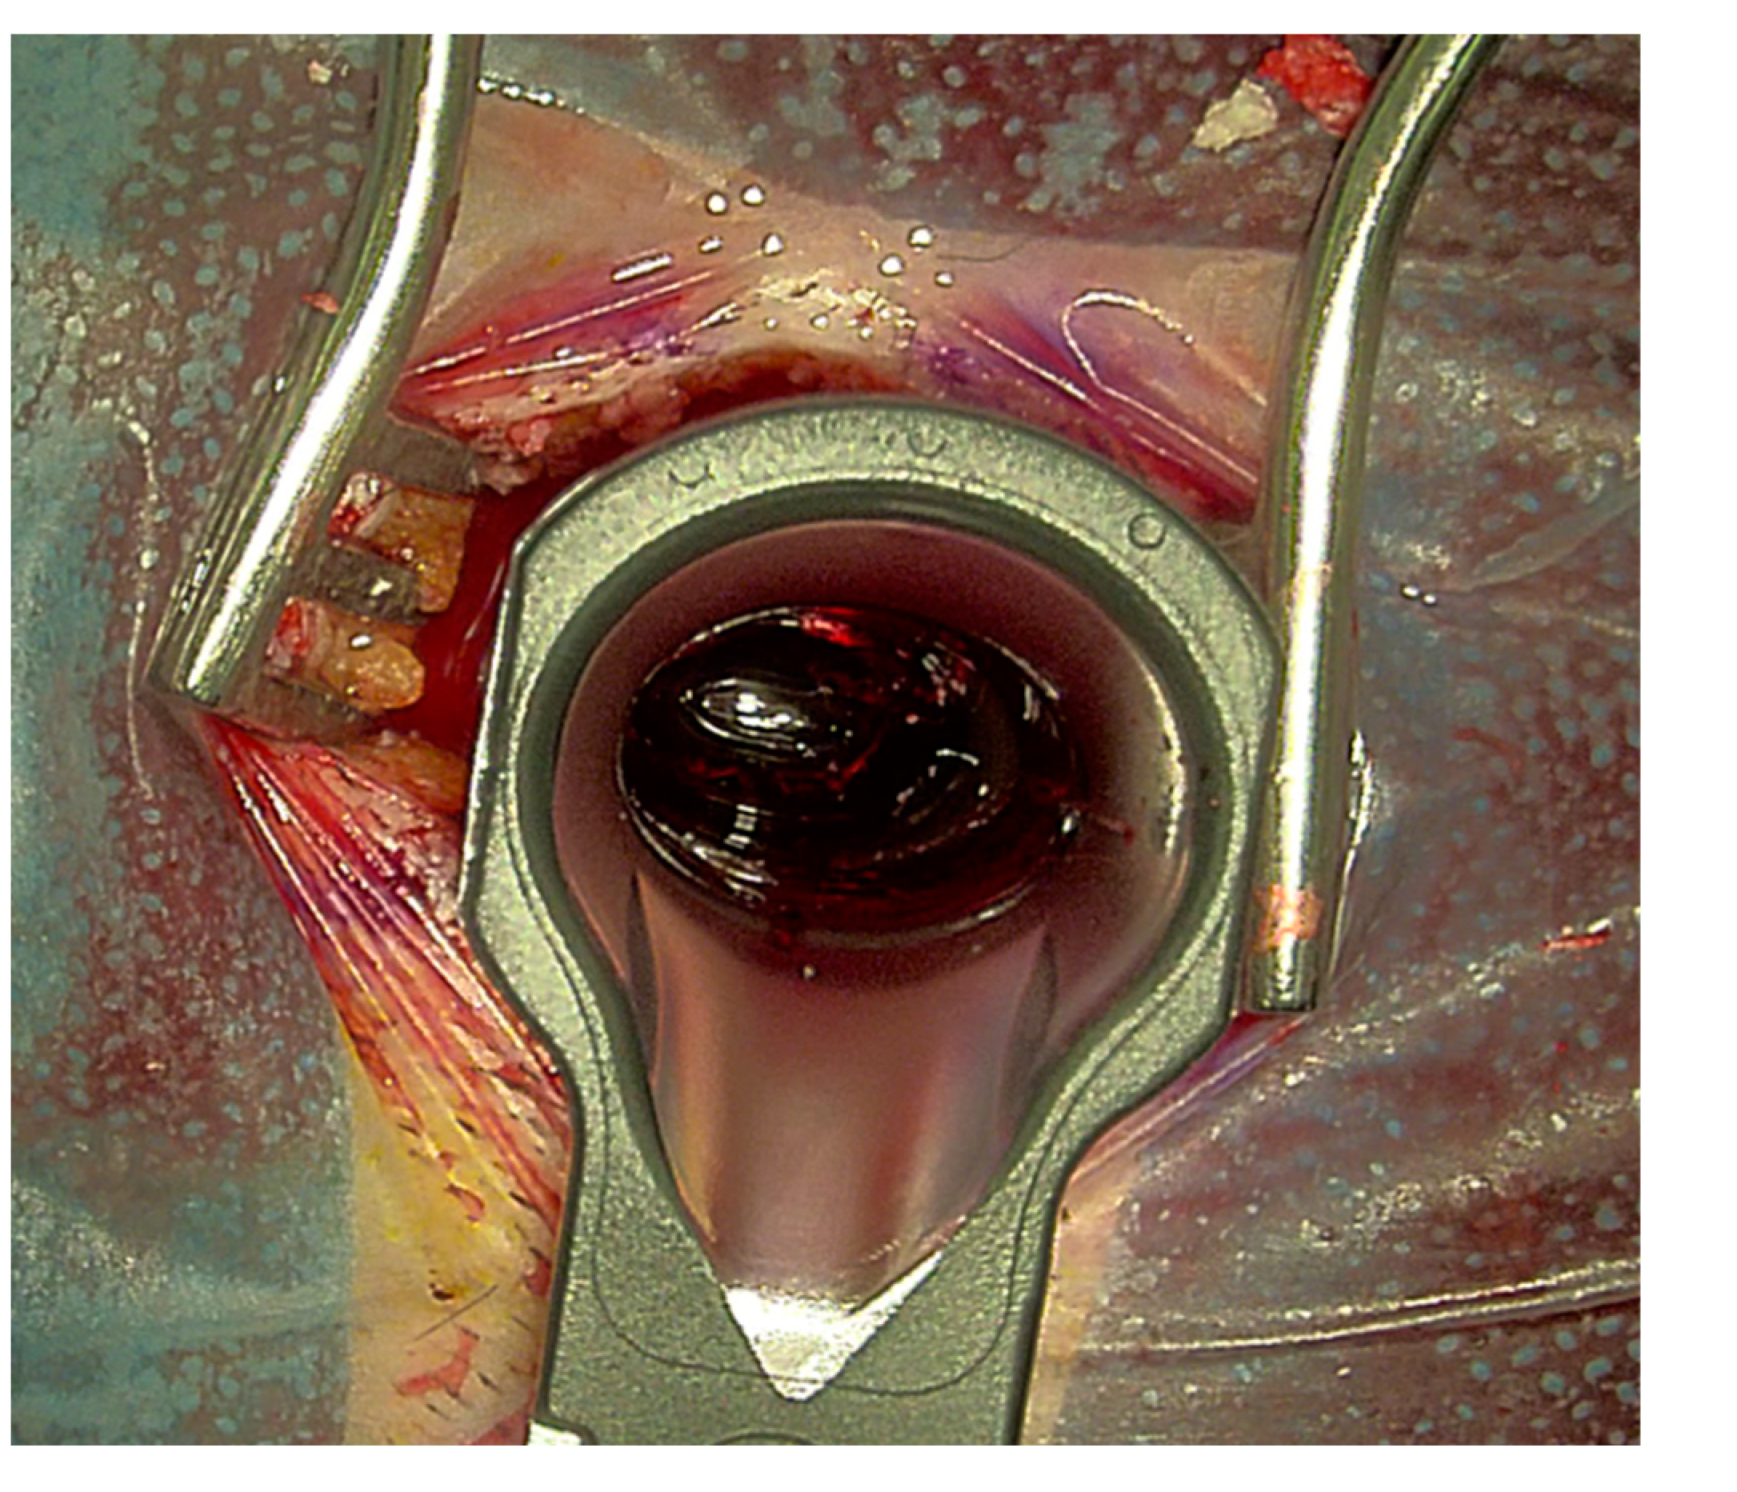

Figure 5. Evacuation of an intracerebral hemorrhage with the assistance of tubes. Intraoperative visualization of the hemorrhage during Aeos surgery.